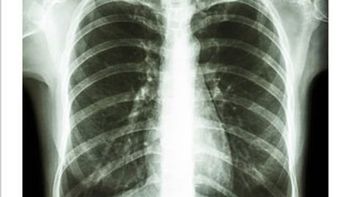

Revised guidelines support low-dose CT screening for patients between ages 50 and 80 with 20-pack year smoking histories – a move that lowers the screening age and, potentially, incorporates more high-risk individuals.

Research data reveals using LDCT with patients who have never smoked – but who are still at high risk – is effective for lung cancer screening.